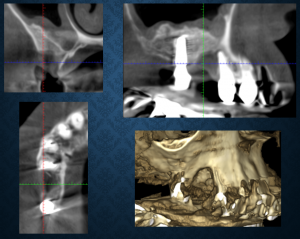

今日はインプラントが後に入ることが前提(インプラントを入れたいが骨幅が足りない状況でした)の造骨処置を行いました。患者さんは他院でマイクロスコープ下での根管治療を自費でやっていたのだそうですが、一向に治らない、治療が進まない、説明もなく歯を抜かれた、インプラントは骨がないからできない等々、様々な不満を抱えて2年ほど前に来院されました。咬合や根管治療の予後不良、上顎両側臼歯部欠損など、多くの問題を抱えていましたが、シンラシステムによる咬合分析とそれに基づいた診査診断、建築士が図面に設計図を描くように、模型上に蝋で治療設計を具現化していきました。要再根管治療歯が2本あり、1本は治癒しましたが、もう1本は残念ながら予後不良で抜歯となりました。もともと存在していた根尖病変が比較的大きかったため、抜歯後の骨回復は十分でないと予想していました。既にほかの部分である天然歯の補綴、上顎臼歯部にインプラント治療をするうえで骨不足確認後、サイナスリフト(副鼻腔内造骨処置)を行い、その後のインプラント治療は終了しており、残る部分はここのみとなっていました。前歯は手を付けないでほしいとのことだったので完全とは言えませんが、ほぼフルマウスリコンストラクションのケースでした。